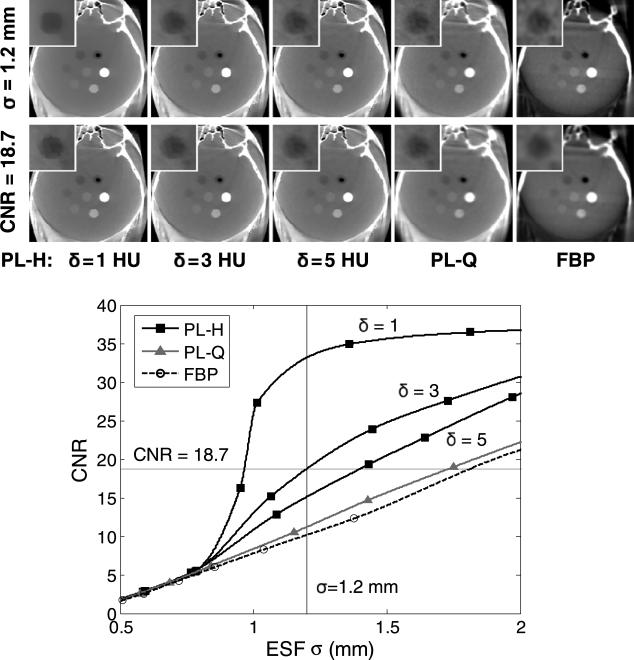

The effect of reconstruction algorithm and parameter selection on image noise and spatial resolution is demonstrated in figure 5 for a fixed dose of 3.3 mGy (1.25 mA × 64 s × 0.041 mGy/mAs), showing the CNR of the low-contrast sphere as a function of ESF. The conventional noise-resolution tradeoff is seen with FBP: as the cutoff frequency is reduced, leading to a smoother edge, the CNR increases accordingly. Perhaps surprisingly, PL-Q follows a tradeoff close to that of FBP due to its uniform application of smoothing, with only a small CNR gain over FBP. In fact, PL only departs from the conventional tradeoff when the Huber penalty is applied with a sufficiently small δ, with a sharp increase in CNR beginning at around σ = 0.8 mm. Therefore, PL-H provides a CNR advantage only at lower spatial resolution for low-contrast edges (e.g., σ > = 0.8 mm for 40 HU contrast in the head), which suggests the visualization of soft-tissue structures is improved by PL-H at lower spatial resolution rather than at higher spatial resolution. For very small δ, such as δ = 1 HU, the sharp increase in CNR becomes especially pronounced, providing a ‘kink’ in the curve that can be attributed to the edge-preservation properties of the Huber penalty. However, over-regularization with such small δ can lead to a blocky appearance of the sphere and patchy texture in uniform regions. Additionally, while larger σ yields a larger relative gain in CNR for PL-H over FBP, excessive image blur should be avoided. For example, the reconstruction methods can be compared at equivalent spatial resolution of σ = 1.2 mm, demonstrating the noise reduction with PL-H at lower δ, but with δ = 3 HU chosen as a reasonable middle-ground for the Huber penalty in terms of a reasonable gain in CNR while avoiding a blocky appearance to low-contrast features. Additionally, although the spatial resolution for low-contrast tissues was reduced in order to improve CNR, PL-H maintains the sharpness of higher contrast features, unlike PL-Q or FBP which apply more uniform smoothing across the object. On the other hand, when the reconstruction methods are compared at equivalent CNR, it is clear that PL-H with larger δ, PL-Q, and FBP require greater image smoothing (in that order), but that δ = 1 HU produces unrealistic, rough edges. Therefore, the apparent gain suggested by metrics such as CNR must be balanced relative to the qualitative acceptability of the images, which may exhibit characteristic blocky or patch textures associated with over-regularization.

Figure 5.

Head phantom showing the noise-resolution tradeoff for different reconstruction methods (3.3 mGy). As β is increased for PL-Q, both CNR and ESF width increase, achieving roughly the same tradeoff as decreasing fc,u in FBP. The Huber penalty (PL-H), on the other hand, departs from the conventional tradeoff. At fixed spatial resolution (σ = 1.2 mm, top row of images), PL-H offers the lowest image noise, and at fixed CNR = 18.7 (second row of images), PL-H offers the highest spatial resolution, but qualitative assessment indicates that reducing δ too much (e.g., δ = 1 HU) results in a blocky, more piece-wise constant appearance in the image. Display window [0.009, 0.028] mm–1 for the full FOV and [0.016, 0.021] mm–1 for the inset.

Other artifacts appear as previously reported with FBP reconstruction (Schafer et al 2011)—e.g., lateral streaks associated with the incomplete orbit (~178° arc) and truncation artifacts (image intensity differences at the edge of the FOV). The quantitative analysis of ESF and CNR avoided the effects of these artifacts by, for example, selecting the noise ROI in a largely artifact-free region. Nonetheless, PL-Q and PL-H are seen to provide the additional benefit of greatly reducing these artifacts in comparison to FBP, with the inherent ability to account for the incomplete orbit (or more generally, an arbitrary orbit) and to diminish the effects of truncation within the C-arm FOV. In particular, we will henceforth focus on PL-H with an appropriately selected δ (viz., δ = 3 HU for the head) due to its improved performance over PL-Q.

At matched spatial resolution (σ 1.2 mm) in PL-H (δ = 3 HU) and FBP across a range of levels, it becomes clear that PL-H provides a boost=in CNR regardless of dose, as shown in figure 6. Although visualization of the low-contrast sphere is reduced at lower dose, PL-H maintains an advantage over FBP for this task, which is representative of the size and level of contrast needed to detect, for example, an ICH. A power-law curve fit (axb + c) was applied to the measured CNR in figure 6, and while it is generally an appropriate fit+for FBP, it may be less suitable for PL-H. Nonetheless, it can be seen that PL-H simultaneously offers higher CNR at lower dose. For example, PL-H at 3.3 mGy offers ~50% higher CNR than FBP at 6.6 mGy. As demonstrated above, PL-Q shows little or no improvement over FBP in this regard, and it is the edge-preserving PL-H that departs from the conventional tradeoff. The ability of PL-H to suppress noise appears relatively better at higher dose, where the contrast target is more easily differentiated from the image noise, allowing for stronger noise reduction. The greater relative advantage of PL-H over FBP emerges at doses of 1.7 and 3.3 mGy in this scenario. Despite improvements in CNR, low-dose limits must of course be considered alongside assessment of the clinical acceptability of the images, e.g., noise in the 0.8 mGy images may be too high to be clinically acceptable, even with PL-H.

Figure 6.

Head image reconstructed with PL-H versus FBP over a range of dose levels. At matched spatial resolution, PL-H maintains superior CNR over FBP for the low-contrast target. For example, PL-H at 3.3 mGy yields a 50% higher CNR than FBP at 6.6 mGy.